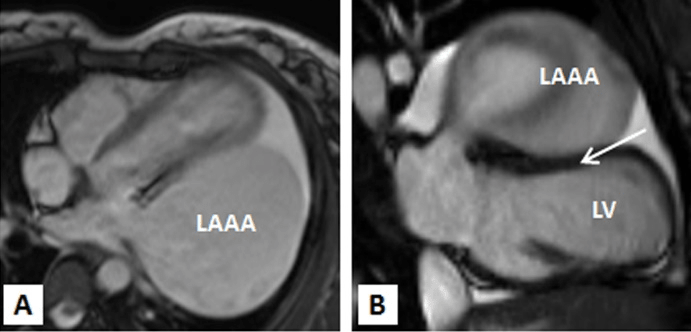

Multi-slice row computed tomography and magnetic resonance imaging was done that showed a large contrast-enhancing chamber continuous with the left atrium via a wide neck. The left atrium was grossly normal in size itself and a wide neck of 4.0 cm lead to a large aneurysm measuring 8.33 x 7.01 x 4.0 cm. The left anterior interventricular coronary artery was closely seen in relation to the communicating neck and was normal as were the other coronaries. Lower down, the aneurysm was lying adjacent to the lateral wall of the left ventricle which showed normal wall thickness and cavity size. The pulmonary veins were located at their normal anatomical positions with no evidence of stenosis (Figures 3A-3C, 4A, 4B). Considering the size of the left atrial appendage aneurysm with supraventricular arrhythmias and deteriorating clinical symptoms, the patient was medically stabilised and was considered for aneurysectomy of the left atrial appendage. The operation was performed under normothermic cardiopulmonary bypass using angled venous cannulae (Edwards Life Sciences Research Medical Inc, West Midvale, Utah) into the superior and inferior caval veins and aortic cannulation. St.Thomas-II cold blood cardioplegic solution (1:4) and topical hypothermia was used for myocardial preservation. The right pleural cavity was opened, and the heart was dislocated within the right pleural cavity.

Figure 4A,4B: MRI TRUFISP (true fast imaging with steady-state free precession) four chamber (A) and vertical long axis (B) view image revealing the left atrial aneruym is indenting the anterolateral wall of left ventricle.